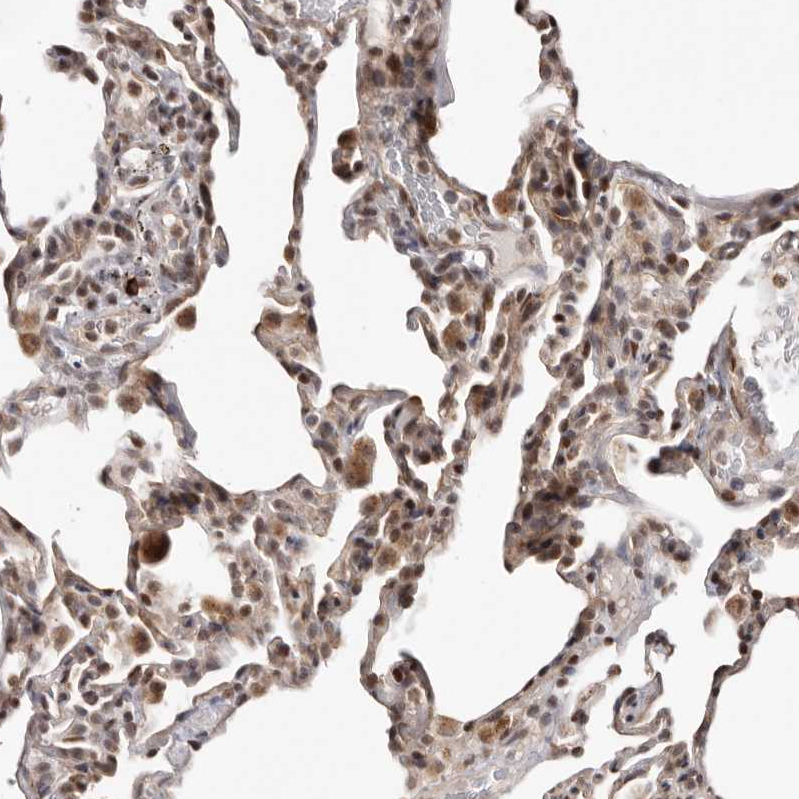

Immunohistochemical staining of human lung shows strong cytoplasmic-nucleus positivity in macrophages.